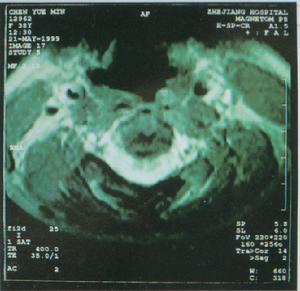

普通胸片見左心室增大,但也可在正常範圍,晚期可有左房增大、肺淤血。主動脈不擴大,X線或核素心血管造影可顯示室間隔增厚,左心室腔縮小。核素心肌掃描可顯示心肌肥厚的部位和程度。